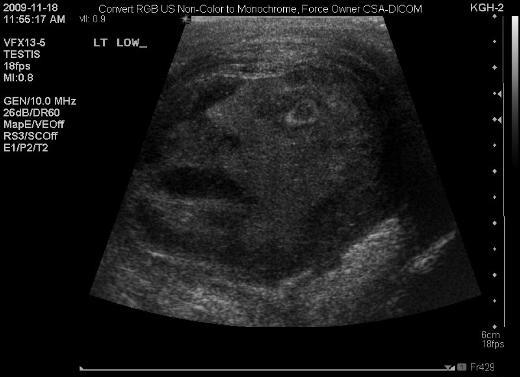

2. Kanada'da çekilen bu ultrason görüntüsü, görenleri şoke ediyor. Bir erkeğin testis kanseri olup olmadığı tespit etmek isteyen doktorlar, ultrason yöntemine başvurdu. Ortaya ise sanki çığlık atan erkeği andıran bu görüntü çıktı.

Kanada'da çekilen bu ultrason görüntüsü, görenleri şoke ediyor. Bir erkeğin testis kanseri olup olmadığı tespit etmek isteyen doktorlar, ultrason yöntemine başvurdu. Ortaya ise sanki çığlık atan erkeği andıran bu görüntü çıktı.